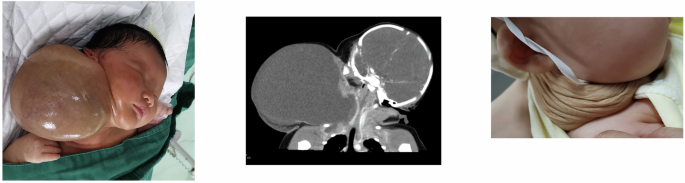

Typical images of patients in the two groups are shown in Figs. 1 and 2.

After the treatment, the lesion decreased significantly and the compression at the neck was relieved.